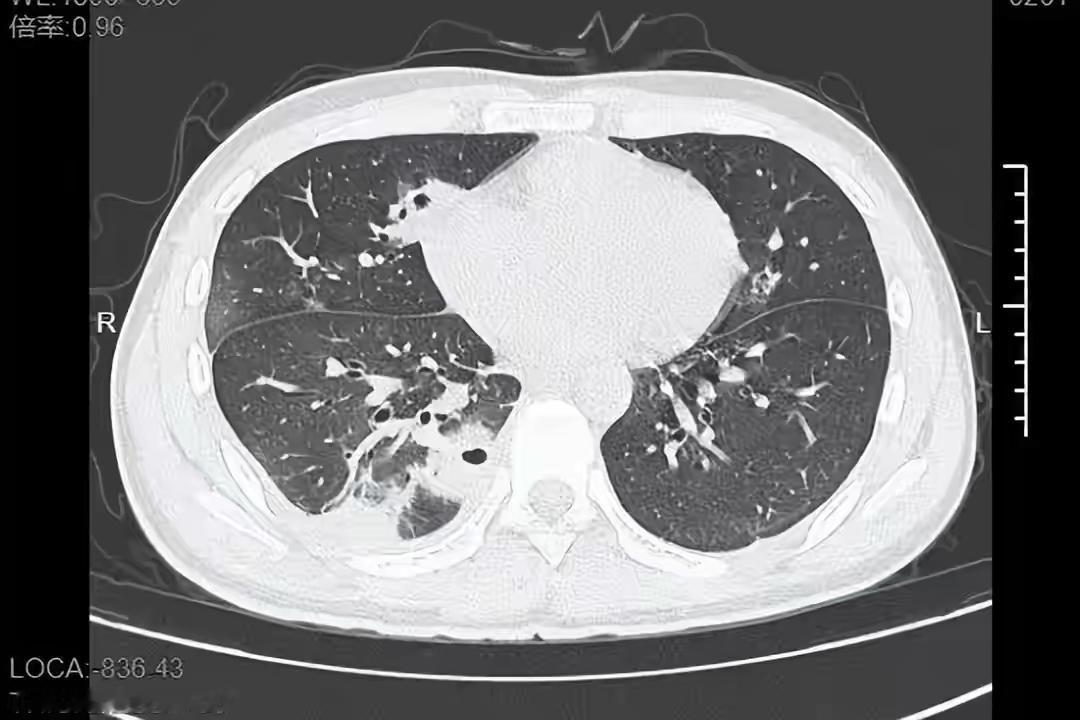

挤一颗痘痘竟致肺里现十几个空洞!大二学生的惨痛教训 20岁的大二学生小林为备考熬夜后,脸部冒出一颗黄豆大小的红肿痘痘。因觉得影响美观,他未洗手便对着镜子将其挤掉,当时看着脓水流出还倍感清爽。 然而几天后,痘痘不仅持续化脓,小林还出现发烧、咳嗽、咳痰等症状,退烧药仅能暂时缓解不适,右下胸更是传来针刺般的疼痛,深呼吸、咳嗽时疼得直冒冷汗。熬至第三天,体温升至39℃的小林紧急前往宁波大学附属第一医院就诊。 接诊的丁群力主任医师通过CT检查发现,小林肺内出现十几个空洞,部分肺组织已坏死,确诊为血源性肺脓肿。细菌培养和基因检测显示,其血液中检出的金黄色葡萄球菌是“元凶”——该细菌原本存在于皮肤表面,而小林挤的痘痘位于脸部“危险三角区”,未洗手的操作让细菌在挤压压力下进入血管引发败血症,进而随血流侵入肺部,侵蚀肺组织导致严重感染。医生提醒,脸部危险三角区的痘痘切勿随意挤压,皮肤出现感染需及时科学处理,避免引发致命风险。